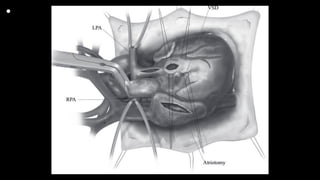

• Figure 2 The aorta, SVc, and inferior vena cava are cannulated, and the

patient is placed in mildly hypothermic cardiopulmonary bypass (32-

341C). The aorta is cross clamped, cardioplegia is delivered into the aortic

root, and attention paid to a prompt diastolic arrest. The caval tapes

are snared, a right atriotomy is performed, and a left ventricle vent placed

though the PFO. The intracardiac anatomy (VSD, RVOT muscle

bundles) is inspected. After control of the branch PAs, the MPA is incised

longitudinally using the previously placed distal midpoint suture as

a guide (it is easy to veer toward the LPA and thus create a problem at the

distal MPA). If a decision has been made to make an infundibular

incision, the RVOT is opened over approximately 1 cm at the point of

greatest stenosis. RPA = right pulmonary artery; LPA = left pulmonary

artery; VSD = ventricular septal defect.